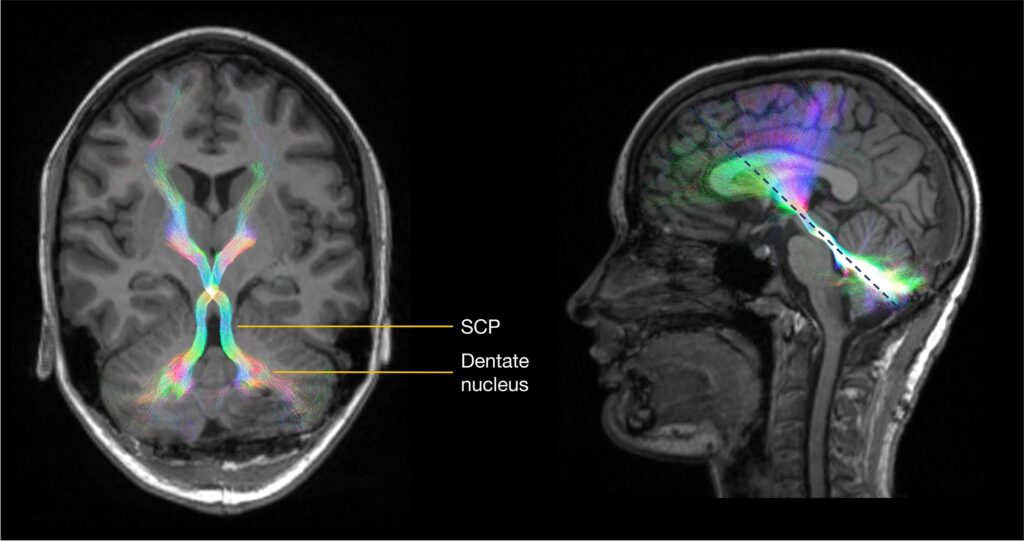

CMS. Bilateral DRTC tract streamlines (in a directionally encoded color scheme) are overlaid on T1-weighted images. Tracts in

their long axis (left) are indicated by the dotted blue line (right). Figure is available in color online only.

It is now widely accepted that disruption of the proximal efferent cerebellar pathway (pECP)—the dentate and other deep cerebellar nuclei, and the proximal dentato-ru-bro-thalamo-cortical (DRTC) tract as it ascends throughthe superior cerebellar peduncles (SCPs) (Fig. 1)—is closely linked to the development of CMS. The cerebellum communicates with other parts of the brain through thecerebellar nuclei. Diffusion signal abnormalities indicating damage to white matter bundles in the SCP were first demonstrated in 2009.5 Similar voxel-based results have been replicated by other groups since <sup6,7 and include dif- fusion abnormalities of the pECP on intraoperative MRI scans, which were significantly associated with CMS,with bilateral involvement of pECP being highly specific.7 Hypertrophic inferior olivary degeneration (by way of the central tegmental tract) is another characteristic imaging feature in patients with CMS (Fig. 2).

8 Recent studies have also identified damage to the fast-igial nucleus as a strong predictor of CMS.9 Diffusion tractography has revealed the underlying somatotopy of the SCP in children10 and shown that SCP damage in CMS may be highly focal.11 These diffusion imaging studies are complemented by modern lesion-symptom mapping approaches that demonstrate higher lesion loads in the cerebellar outflow pathway in children with CMS compared to those without.12,13